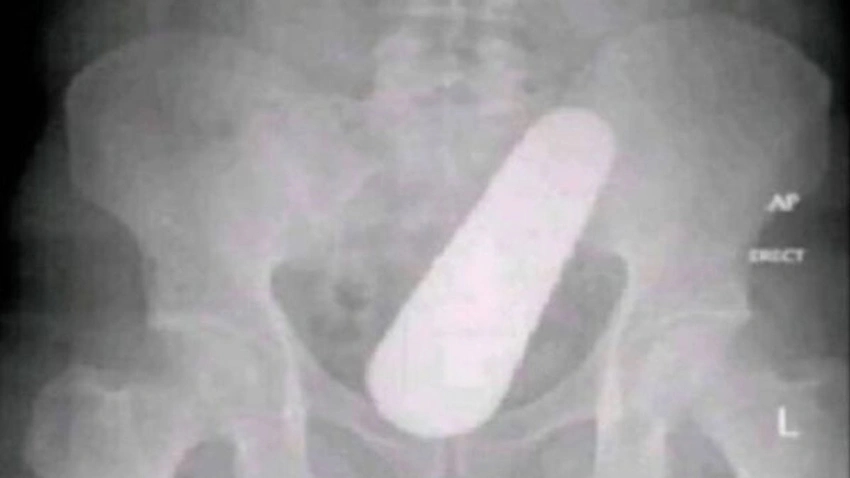

40 yaşındaki bir adam, ağrı şikayetiyle doktora başvurduğunda, asla beklemediği bir durumla karşılaştı. Röntgen çekildiğinde, adamın rektumunda büyük bir yabancı cisim keşfedildi. Doktorlar, adamı ameliyata almak için hemen hazırladılar. Operasyon sırasında, doktorlar adamın rektumundan büyük bir cisim çıkardılar. İnanılmaz ama gerçek, çıkan cisim bir salatalıktı. Adamın rektumunda nasıl bir salatalık olduğu hala açıklanamıyor. Ancak, adamın evde çok fazla salatalık yediği teorisi ortaya atıldı.